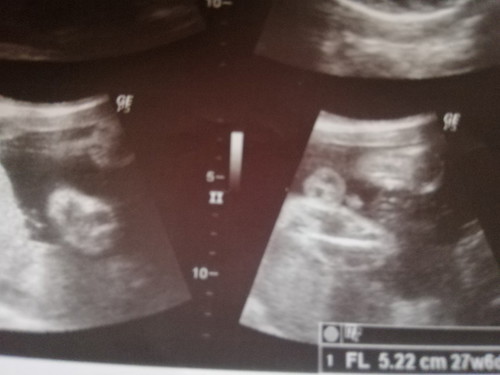

gender

baby boy or baby girl? ?

I think its a baby boy. You can see his testicles hehe

Boy. Nakasilipnapo si junior ππ

Boy po.. Kita ko ung balls :D

Parang Girl po kasi may hiwa

Girl,. May hiwa po